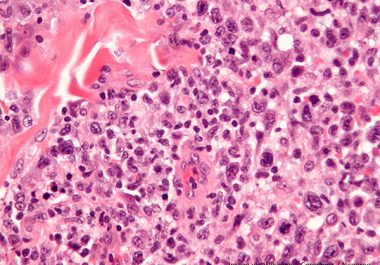

The FDA approved a molecularly targeted therapeutic to treat certain pediatric patients and young adults with anaplastic large-cell lymphoma, a rare form of non-Hodgkin lymphoma.